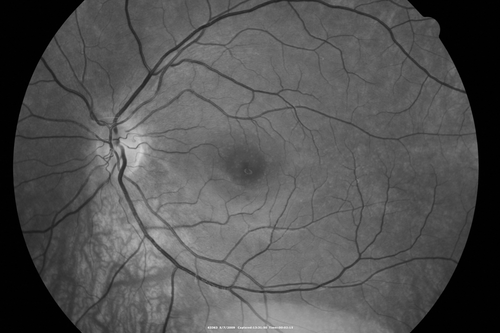

Cuticular Drusen - 26 year old female - Glomerulonephritis

VA 20/25 OU. Images are over 4 years

Cuticular Drusen 26 year old woman with history of Glomerulonephritis